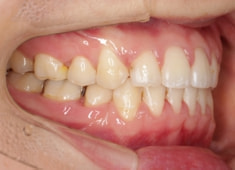

治療後(2年9ヶ月後)